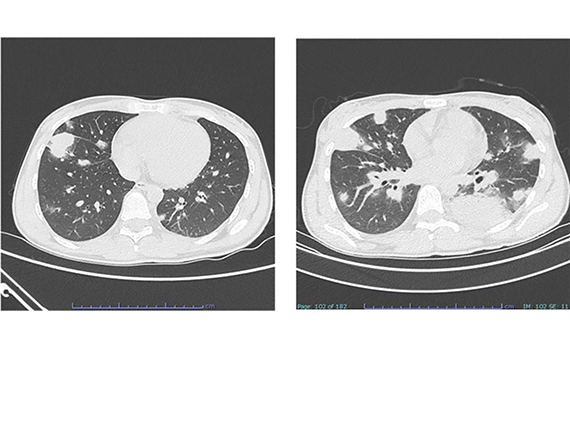

• Transthoracic imaging-guided needle biopsy: 5 years’ experience in Indonesia

Ginanjar Arum Desianti, Dicky Soehardiman, Mia Elhidsi, Tina Reisa, Mohamad Fahmi Alatas, Wahju Aniwidyaningsih, Prasenohadi

DOI: https://doi.org/10.5826/mrm.2025.1046